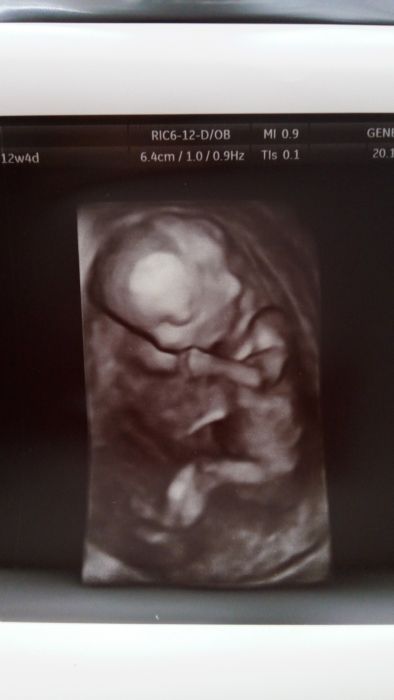

Holky tak jsme doma ze screeningu. Čekali jsme tak dlouho, až se z toho mimi postavilo na hlavu

takže sme ho museli otáčet. Ale všechno je v pořádku. Otáčením se vzbudilo a teda jako naschvál se mrskalo jako o život. A teda předběžně prej kluk, ale já si stejně myslím že se to ještě změní